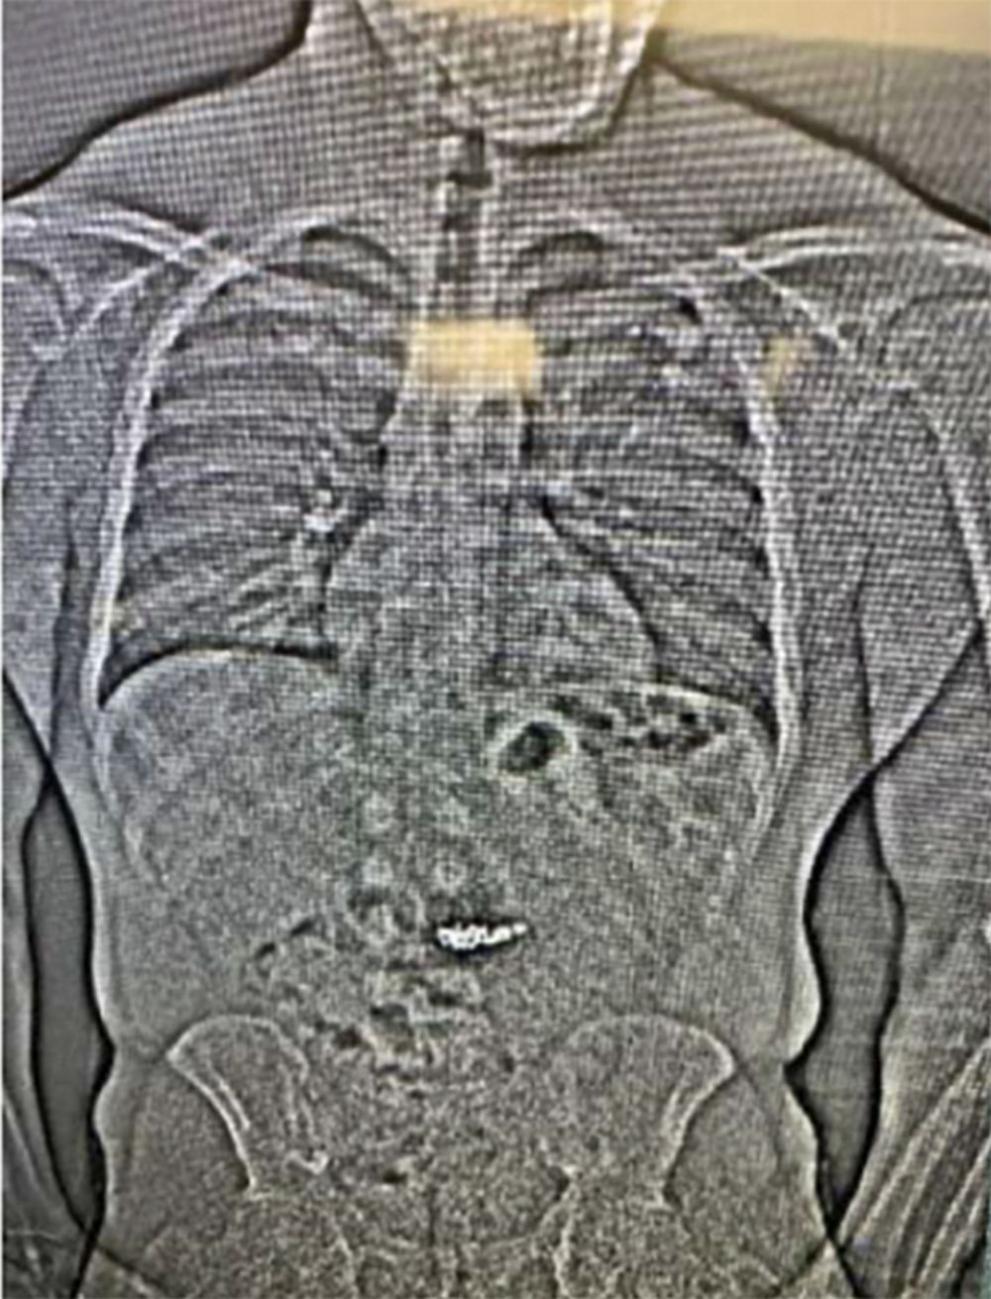

След изработен скенер в пандиза, управляващите разкрили изчезналите бижута в стомаха му . „ Тези непознати обекти евентуално са обеците от Tiffany & Co. , само че ще би трябвало да бъдат събрани след прекосяването им през храносмилателната система на Гилдър “, се показва в отчета.